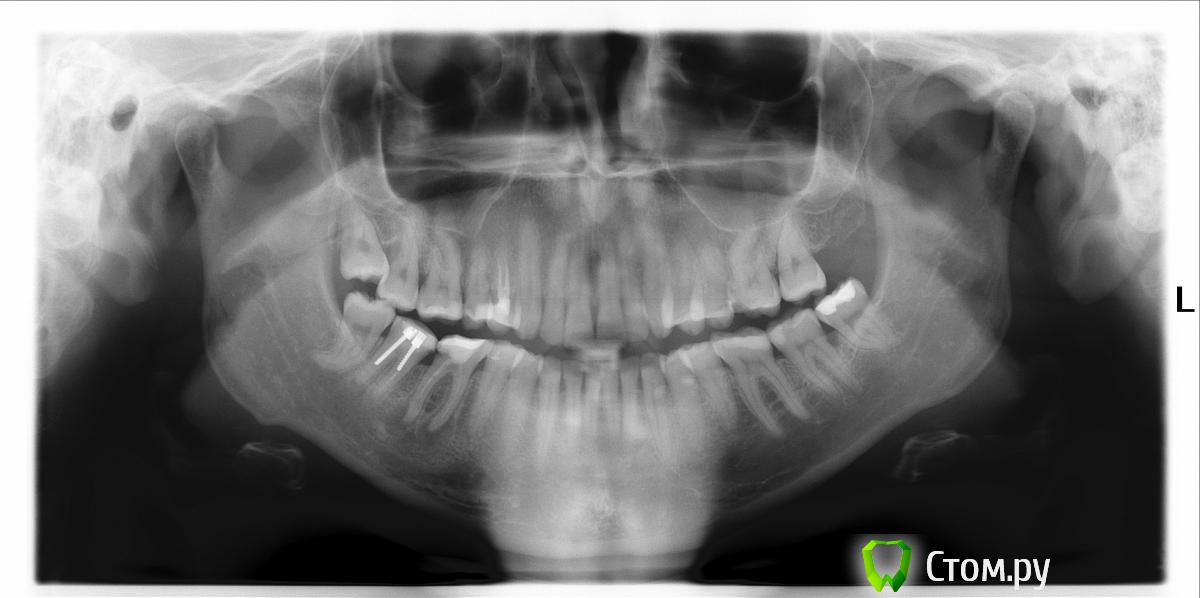

Kolchanov Опубликовано 30 октября, 2014 Автор Поделиться Опубликовано 30 октября, 2014 Одолел, блин, стекловолокно. Как хорошо, что доктор метапекс в качестве силера использовал. Вся задача состояла в том, чтобы оставить за что ухватиться.http://s020.radikal.ru/i709/1410/32/d113acd3a59a.jpghttp://i008.radikal.ru/1410/f4/365fbbe8f6ef.jpghttp://i062.radikal.ru/1410/83/cf18693fa37c.jpg 5 Ссылка на комментарий

Гарриевич Опубликовано 30 октября, 2014 Поделиться Опубликовано 30 октября, 2014 Отлично др. Колчанов, теперь делитесь последовательностью действий) Ссылка на комментарий

M@estro Опубликовано 30 октября, 2014 Поделиться Опубликовано 30 октября, 2014 Отлично др. Колчанов, теперь делитесь последовательностью действий) опили да вынул Штиглицами) Я так делаю,судя по фото - Константин тоже Ссылка на комментарий